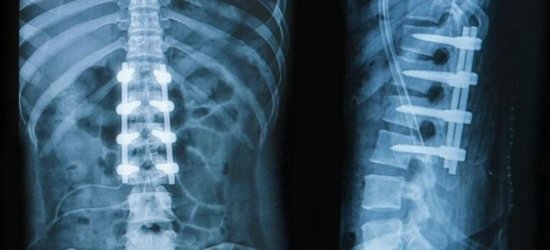

Рентгенологическое обследование выявит изменение высоты межпозвонковых дисков, возможные остеофиты — разрастания костной ткани, вызванные неправильно распределенной нагрузкой на позвонки, изменение формы самих позвонков.

Компьютерная томография и МРТ покажет выбухание межпозвонкового диска, кальцификаты (участки обызвествления), стеноз позвоночного канала.

Сегодня на смену этим двум исследованиям постепенно приходит УЗИ позвоночника, позволяющее обнаружить аналогичные изменения, не подвергая пациента чрезмерной лучевой нагрузке.